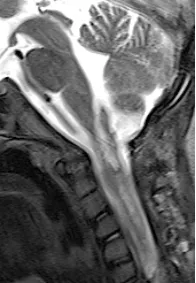

虽然是间变型少突胶质细胞瘤,但海迪在手术+化疗的综合治疗下,随访11年,她长大了,身体状态良好,连为她手术的巴教授也十分高兴。

术后MRI